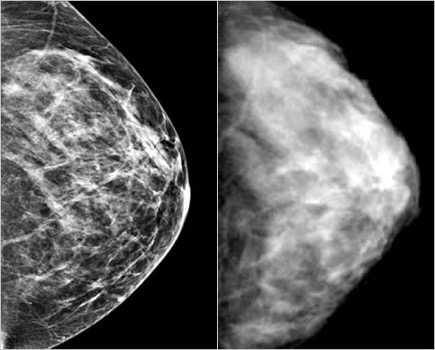

In figuur 3 staan twee vlak na elkaar genomen borstfoto’s (mammogram) van dezelfde vrouw. Rechts een ouderwetse afgedrukte Röntgenfoto en links een digitale foto. Wat zal het verschil zijn tussen de ouderwetse en moderne foto?

Het effect is precies hetzelfde als in het voorbeeld met de landkaart. Als de foto’s of scans die wij maken beter worden, gaan we onherroepelijk meer afwijkingen vinden die gemiddeld kleiner zijn. Het geldt dus voor borstfoto’s, maar ook voor een CT-scan van de longen in vergelijking met een gewone longfoto. En het geldt ook voor de PSA bloedtest in vergelijking met wat we vroeger deden. Ik hoor je al denken: “Dat is toch juist mooi, want dan zijn de kansen op genezing groter.” Maar, dat is helemaal niet zeker: het ‘vroeger is beter’ geloof. Vroeger en kleiner opsporen is niet automatisch beter. Ik kom daar verderop in deze serie uitgebreid op terug.